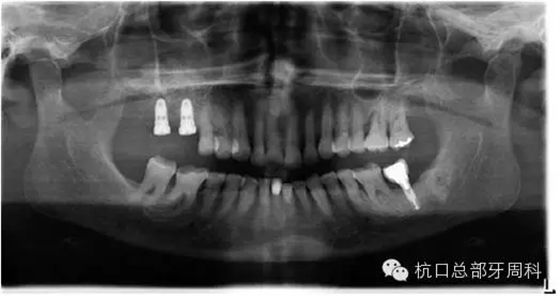

種植后即刻拍片 2005

被診斷為種周炎時全景片 2011

初診時全景片2011.7